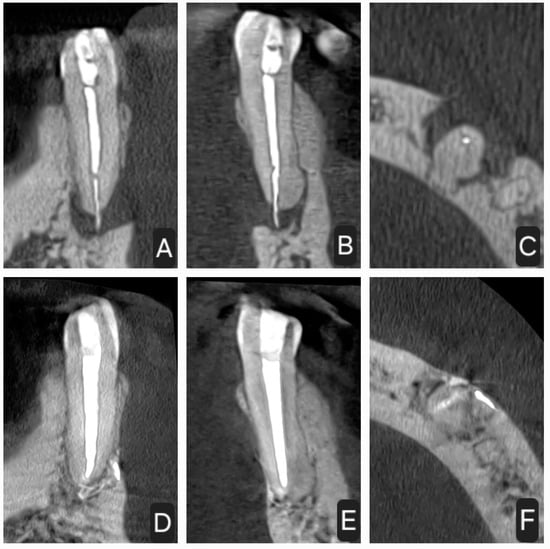

2.1. First Case

2.2. Second Case

2.3. Third Case

2.4. Fourth Case

2.5. Fifth Case

2.6. Control Periapical X-rays